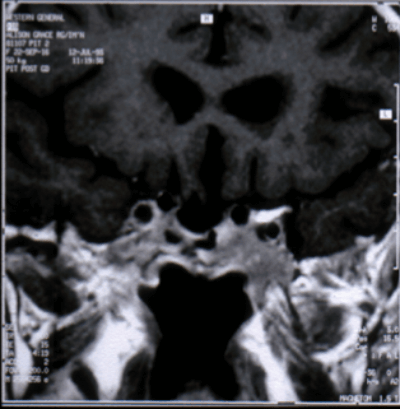

Figure 7: MRI scan coronal image from 1988 showing empty pituitary fossa.

My investigations in 1988 included a MRI scan which showed an empty sella and normal ventricular systems (Figure 7). The prolactin level was >4800 and on discussing this and other aspects of the case with our then Professor of Neurosurgery Professor Douglas Miller (1937-1995) he said “what do you think Zenker’s solution might do to the hypothalamus?” and advised no further investigation noting that the patient at this stage some 60 years post diagnosis was entirely symptom free.